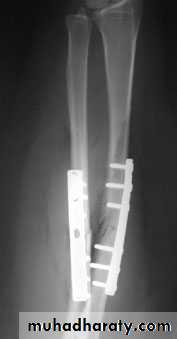

5. External fixation: its usually used in compound fr it means that we use a metal pins that pass through the skin from outside proximal and distal to the fr and after proper reduction the pins are joined together outside the skin by special long bars.The indications of external fixation:

Compound fractures.

Infected fractures as after internal fixation.

Multiple fractures, as an urgent way to stabilize a seriously ill patient.

Fr with nerve or vessel injury.

Fr with extensive soft tissue damage.

Fr of pelvis.

Seriously comminuted and unstable fr.

For bone lengthening.

For joint arthrodesis.

Open reduction of the fr and fixing the fracture with external fixator.

Fractures then stabilized by external fixation until there is good skin cover or until union.

SKIN & SKELITAL TRACTIONSECROW FIXATION

PLATE & SECROW FIXATIONDHS

IMN